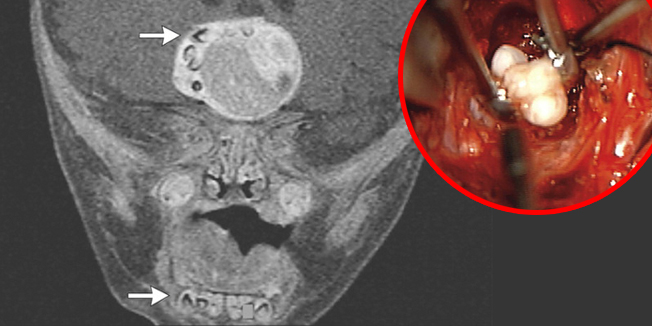

Istražitelji su proučavali tisuće mumija iz starog Egipta i Južne Amerike na kojima su pronašli samo šačicu onih koji su umrli od raka, dok je danas rak odgovoran za svaku treću smrt.

Moderni životni stil i zagađenje zbog razvoja industrije glavni su krivci za nastanak raka. Naime, istraživanje je pokazalo da je učestalost pojave tumora u čovjeka dramatično porasla nakon Industrijske revolucije, posebice to se tiče tumora kod djece. Nadaju se da bi ovo moglo pomoći kako rak nastaje i pridonijeti pronalasku lijeka.

„U industrijskom društvu, tumor je nakon srčani problema, drugi najčešći razlog smrti,“ izjavila je profesorica Rosalie David sa sveučilišta Manchester. „U prirodi nema ničeg što bi moglo uzorkovati nastanak tumora, pa mora da je čovjek kriv za to zbog zagađenja,...